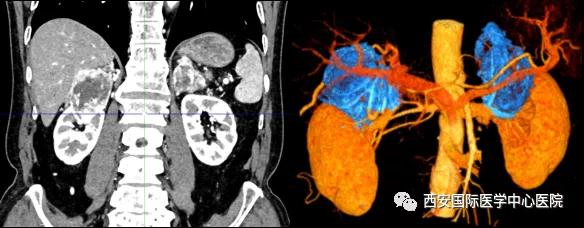

今年七十五歲的患者,來自陜西省商洛市,四月前因腰背部疼痛就診于當(dāng)?shù)蒯t(yī)院,行CT檢查發(fā)現(xiàn)“右腎、雙側(cè)腎上腺占位,前縱膈淋巴結(jié)腫大,雙肺多發(fā)結(jié)節(jié)、胸椎骨質(zhì)破壞,考慮轉(zhuǎn)移瘤”。為進一步診斷治療,患者的兒子帶他來到西安某三甲醫(yī)院,查泌尿系CT提示“右腎占位性病變,多考慮腎癌,雙側(cè)腎上腺多發(fā)轉(zhuǎn)移灶,腹膜后多發(fā)腫大淋巴結(jié)”;行穿刺活檢提示“腎透明細胞癌”;并給予患者口服靶向藥物的治療方案。

患者一家慕名前來到西安國際醫(yī)學(xué)中心醫(yī)院找到楊增悅教授。楊增悅教授仔細看完患者的之前的影像學(xué)及病理資料后,診斷為:右腎透明細胞癌(T4N1M1);并安排他住院。而后,主管醫(yī)生及時為他完善了術(shù)前檢查及評估。7月15日,在麻醉手術(shù)中心柴偉主任、王彬榮副主任、李娟護士長、李瑞剛護士長及全體麻醉手術(shù)中心團隊的有力保障下,成功完成了這臺“大”手術(shù)。

手術(shù)由楊增悅教授主持,舒濤主治醫(yī)師、王東主治醫(yī)師主刀,黃怡醫(yī)師、王平醫(yī)師協(xié)助完成。由于第四代達芬奇機器人更加靈活和精準(zhǔn)的特性,手術(shù)全程順利,尤其是完全精準(zhǔn)的“解鎖”了右腎動脈和右腎靜脈的數(shù)十根交互纏繞的分支血管。術(shù)后患者麻醉恢復(fù)后生命體征平穩(wěn),順利返回泌尿外科普通病區(qū)進一步康復(fù)。